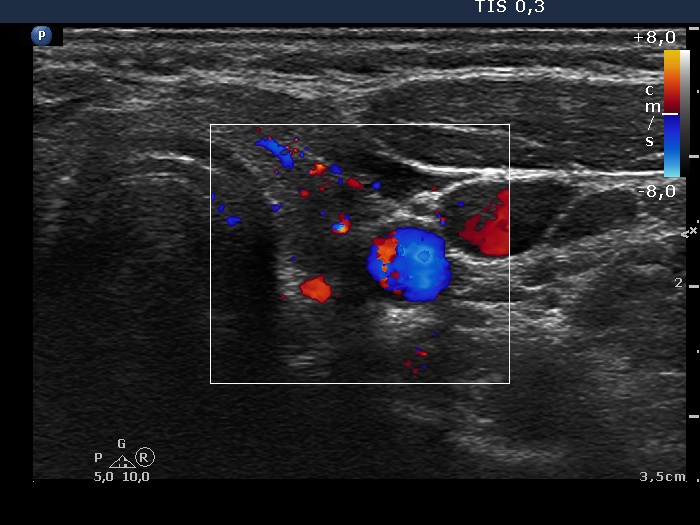

Subacute granulomatous thyroiditis - case 827

16 months after initial investigation (ultrasonographic picture 6)

Left lobe, transverse scan, color Doppler mode. The vascularization is average.